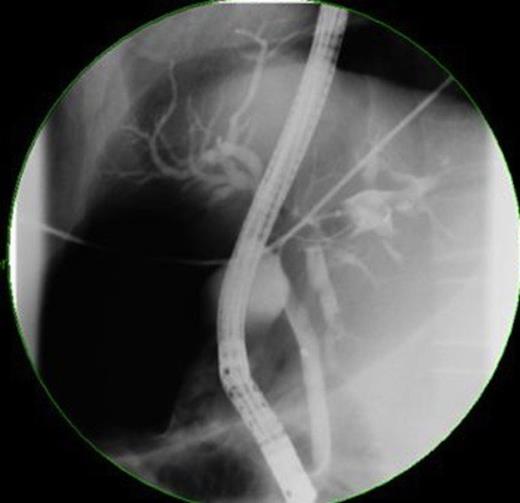

Tumour markers revealed elevated carbohydrate-antigen 19-9 at 807kU/L (normal <40kU/L) suggesting bile-duct disease (1) whilst α-fetoprotein was 4kU/L, within normal range. Magnetic resonance Cholangiopancreatography (MRCP) indicated filling defects in right and left bile ducts (figure 2) and portal vein thrombosis.

ERCP showed casts occupying the hepatic ducts and motile liver flukes were identified. A 10-French stent was inserted and sphincterotomy performed to drain sludge. ERCP histopathology specimens revealed necrotic tissue with eosinophils, although no ova/parasites were visualised. Stool samples did not identify ova so blood samples were taken for serology testing including Clonorchiasis andOpisthorchiasis (results pending at time of publication). Total quantitative immunoglobulins revealed elevated IgA (7.05g/L) and total IgE (874 IU/ml), consistent with a parasitic infection and/or neoplasia. The patient was given 3 doses of 75mg/kg praziquantel for parasites; ciprofloxacin and metronidazole for cholangitis and initiated on warfarin for portal vein thrombosis. Three weeks later his symptoms resolved and stent was removed, ERCP indicating drainage and dead flukes. Despite radiological findings suggesting neoplasia, possibility of liver abscess was still likely. A decision was made not to perform liver biopsy, due to potential for peritoneal tumour seeding if the mass was neoplastic and instead he was monitored on an outpatient basis.

Over the next few months, the man was admitted for repeated cholangitis episodes. ERCP now indicated intra-hepatic duct filling defects (figure 4) and sediment was removed with new stents placed. Repeat abdominal-CT scans indicated the mass was similar in size. Following these presentations, the multidisciplinary team decided to undertake laparoscopic liver biopsy.